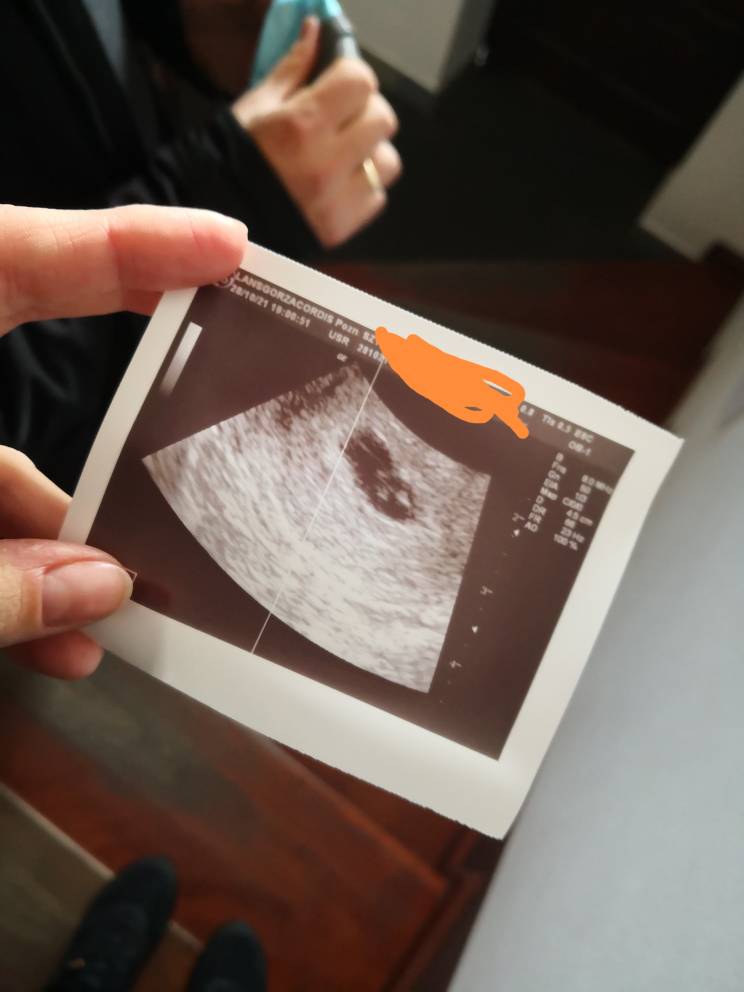

Czy to ciąża bliźniacza?

Hej, czy to ciąża bliźniacza?

Ginekolog nic mi nie powiedział, kazał przyjść za tydzień. Jeszcze tydzień nie minął a ja zaraz zwariuje. :) w jednym bombelku widoczne było serduszko, w drugim nie. Wg usg to 6 tydzień.